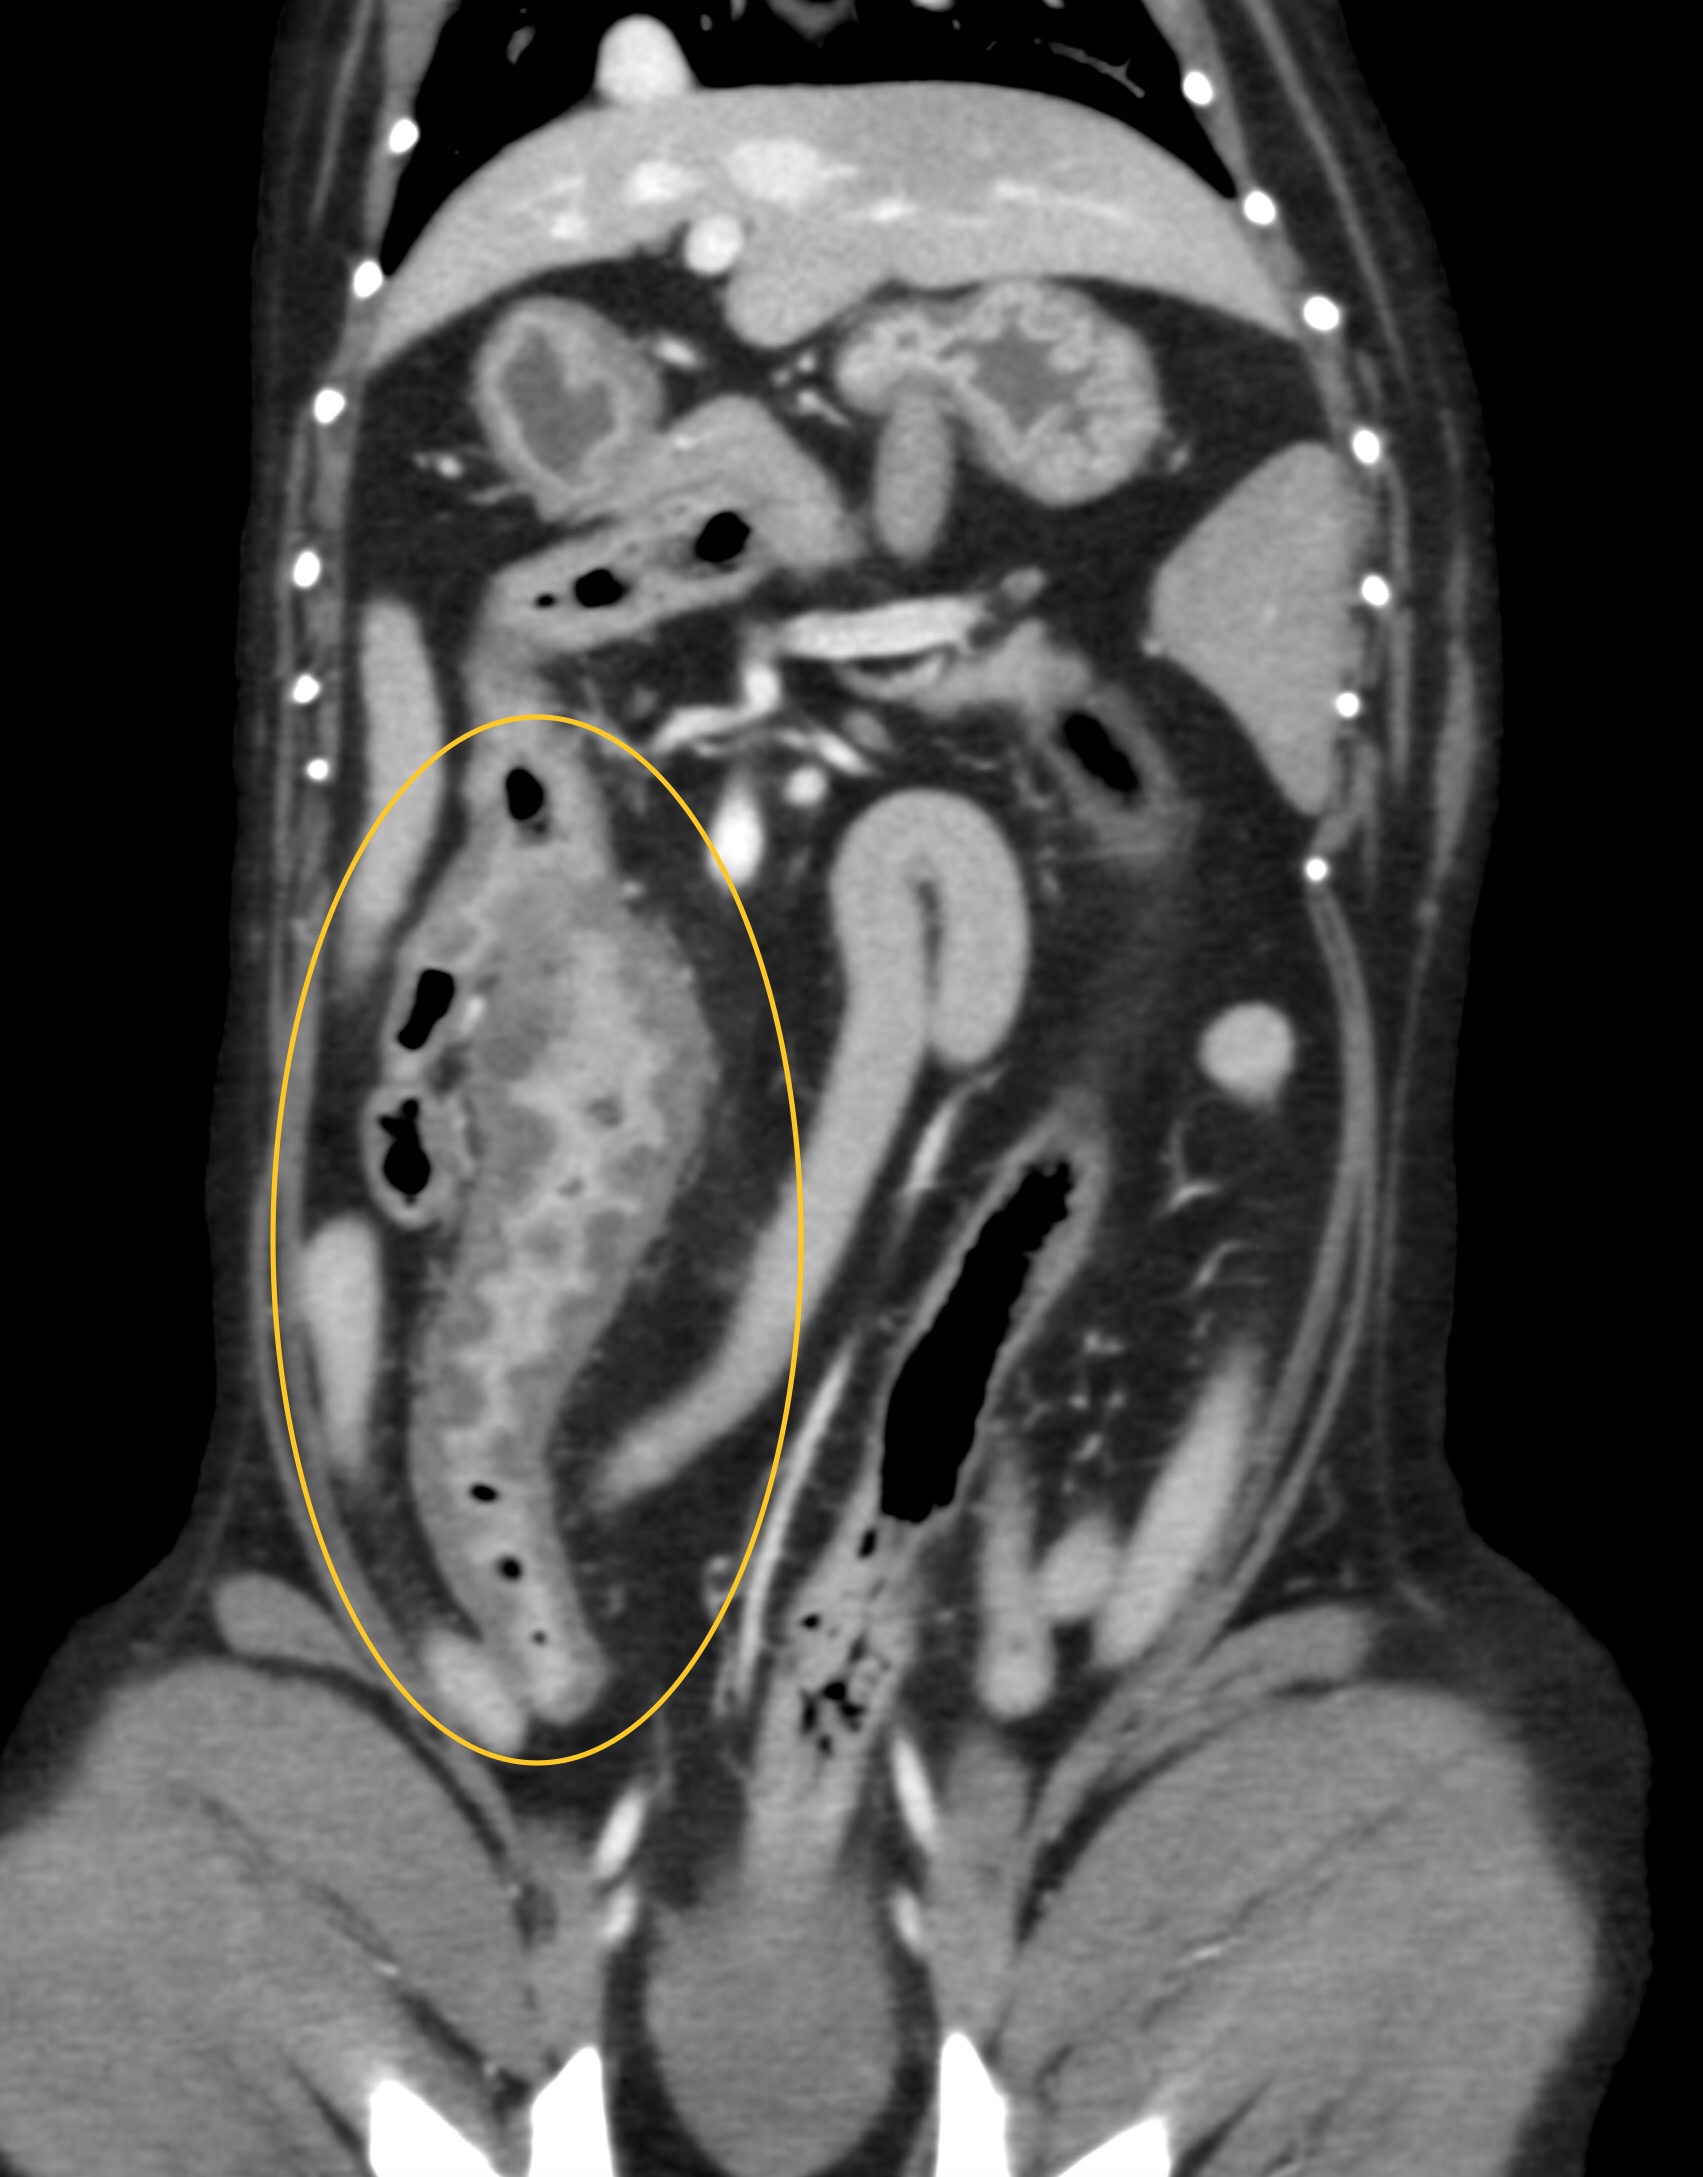

こんにちは。獣医師の永井です。 今回は肉芽腫性腸炎についてです。 肉芽腫性腸炎は、稀な疾患であり、回腸と大腸に…]]>

こんにちは。獣医師の永井です。 今回は肉芽腫性腸炎についてです。 肉芽腫性腸炎は、稀な疾患であり、回腸と大腸に…]]>